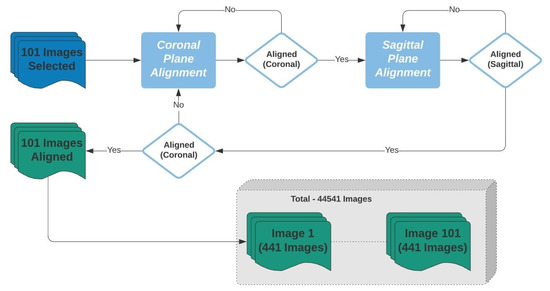

After the alignment, for each of the 101 images, a set of 441 images with inclination angles from −5° to 5°, with 0.5° increments, along the coronal and transverse planes was created. In total, 44541 images were created and were divided into 21 labels. These labels represented the 0.5° of variation in the coronal and transverse planes from −5° to 5°, as shown in Figure 5.

Figure 5.

Figure 7.

Flowchart representing the process of transversal and coronal alignment and database creation.

In this phase, we used the 3D rotation invariant CNN introduced in Section 2.2.2 and detailed in Table 2. To optimize the CNN convergence, computational time, and accuracy, two identical datasets were created using the 44,541 images and represented by 21 labels. Thus, 21 labels represent the rotation in the transverse plane and 21 labels in the coronal 201 plane. 90% of the dataset was used for training, and 10% for validation/testing. Training and testing were performed 10 times. Table 4 shows the analytical performance for these two. It took 30 min in five epochs for the transverse and 70 min in 12 epochs for the coronal CNN to converge using two GPUs.